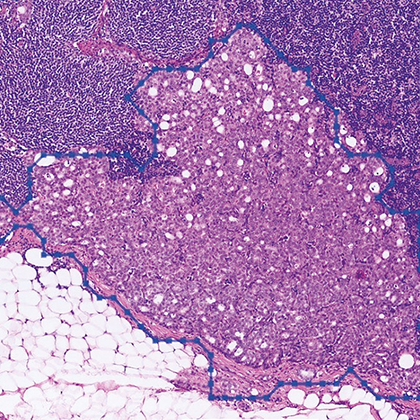

Professor Pheng-Ann Heng has developed an innovative artificial intelligence system using an automated medical image processing technology to offer efficient diagnosis using CT scan and histopathological images. The system, which utilises deep learning algorithms, has been validated on two of Hong Kong’s most prevalent cancers, lung cancer and breast cancer, with high accuracies.